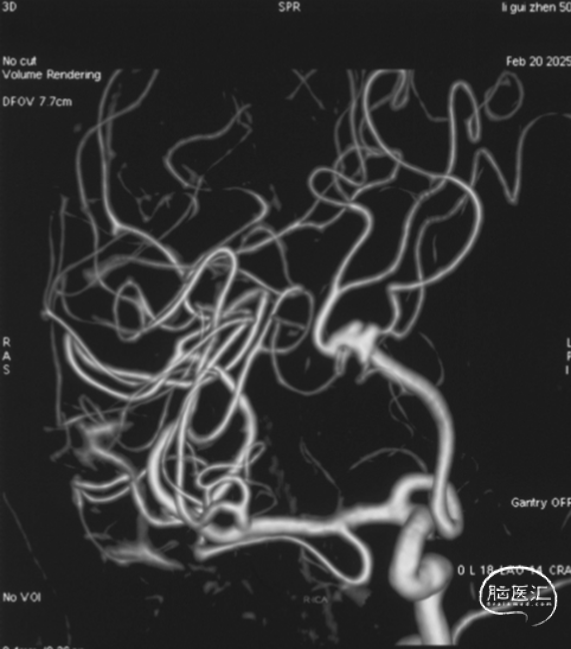

右侧颈内正位造影

右侧颈内侧位造影

载瘤动脉远端血管直径:2.1mm

载瘤动脉近端血管直径:1.8mm

动脉瘤尺寸:瘤颈4.69mm,大小3.25mm*4.21mm*4.24mm;指向右上

近端狭窄:最窄处:0.53mm,远心端2.1mm,近心端2.2mm,长度11.23mm